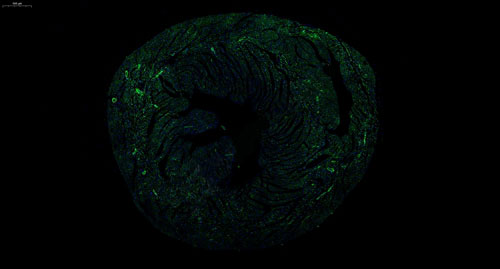

实验结果展示:

小鼠心 普通切片扫描(荧光单标 双色)